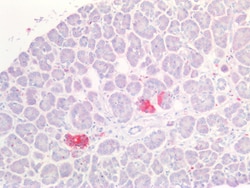

PGP9.5 (Protein gene product 9.5, UCH-L1, PARK5) is a neuron specific protein, structurally and immunologically distinct from neuron specific enolase. PGP9.5 has a molecular weight of 27 kDa and was first identified by high resolution two dimensional PAGE. PGP9.5 is a member of ubiquitin carboxyl-terminal hydrolase family 1 (peptidase family C12) with a ubiquitin carboxyl-terminal hydrolase domain. PGP9.5 is well known for having ubiquitin hydrolase and ligase activities that hydrolyzes small C-terminal adducts of ubiquitin to generate ubiquitin monomers. PGP9.5 is present in neurons and nerve fibers at all levels of the central and peripheral nervous system, in neuroendocrine cells, in segments of the renal tubules, in spermatogonia and Leydig cells of the testis, in ova and in some cells of both the pregnant and non-pregnant corpus luteum. Over expression of PGP9.5 leads to non-small cell lung cancer while decreased expression leads to Huntington disease and Alzheimer disease. Since PGP9.5 is present in cellular inclusions, it can be a useful as a neuronal marker and in the studies of neurodegenerative disorders such as with Parkinson disease.

| Immunohistochemistry (Paraffin), Western Blot, Western Blot | |